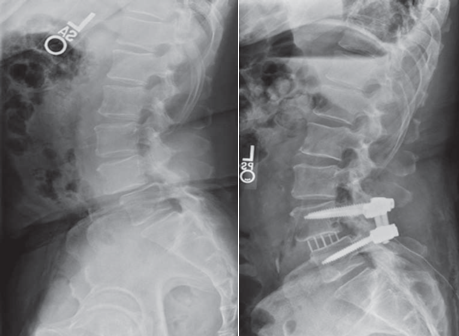

关于手术治疗的研究很多,大多数研究显示手术治疗的近期及远期疗效优于保守治疗。椎板切除减压术和开窗减压术都是腰椎管狭窄可选择的术式。如果切除的骨质过多损害了脊柱的稳定,或者出现了峡部裂型或退行性腰椎滑脱,或者伴有后凸畸形时,那么就需要进行融合术。其他进行融合术的重要指征包括初次融合术后相邻节段的退变、减压术后出现复发性椎管狭窄或椎间盘突出。椎板切除术适用于有严重的、多节段椎管狭窄的老年患者,而开窗手术,包括保留后侧中央结构的双侧椎板切开术和部分的开窗手术,都是可供椎间盘完好的年轻患者选择的术式。